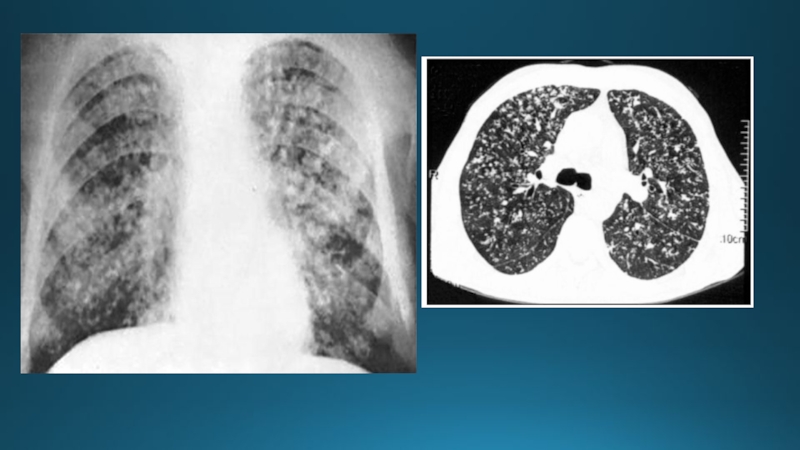

Слайд 61Өкпе туберкулезі

Өкпе туберкулезі – ең жиі кездесетін жалпы инфекциялық, туберкулезді

микобактерия (Кох таяқшалары) қоздырғышымен шақырылатын ауру . Туберкулездің негізгі клиникалық

формасы болып табылады: • Балаларда және жасөспірімдердегі туберкулезді интоксикация.

Өкпе туберкулезіӨкпе туберкулезі – ең жиі кездесетін жалпы инфекциялық, туберкулезді микобактерия (Кох таяқшалары) қоздырғышымен шақырылатын ауру .

Слайд 62Тыныс ағзаларының туберкулез классификациясы

Біріншілік туберкулезді коплекс;

Кеудеішілік лимфа түйіндерінің туберкулезі;

Өкпенің

диссеминирленген туберкулезі;

Өкпенің милиарлы туберкулезі;

Өкпенің ошақты туберкулезі;

Өкпенің инфильтративті туберкулезі;

Казеозды пневмония;

Туберкулема;

Кавернозды туберкулез;

Фиброзды-кавернозды

туберкулез;

Цирротикалық туберкулез;

Туберкулезді плеврит;

Тыныс ағзаларының туберкулез классификациясыБіріншілік туберкулезді коплекс;Кеудеішілік лимфа түйіндерінің туберкулезі; Өкпенің диссеминирленген туберкулезі;Өкпенің милиарлы туберкулезі;Өкпенің ошақты туберкулезі;Өкпенің инфильтративті